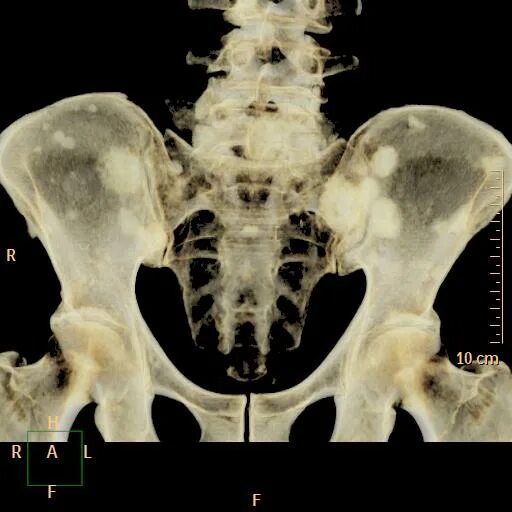

Метастазы по всему скелету